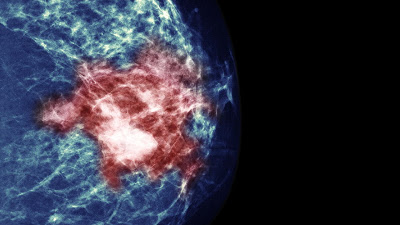

Ο καρκίνος του μαστού αποτελεί το συχνότερο κακόηθες νεόπλασμα των γυναικών στον δυτικό πολιτισμό και τη δεύτερη αιτία θανάτου από καρκίνο, μετά τον καρκίνο του πνεύμονα. Υπολογίζεται, ότι 1 στις 8 γυναίκες θα διαγνωστεί με καρκίνο μαστού σε κάποια φάση της ζωής της. Στην Ελλάδα η συχνότητά του έχει αυξηθεί επίσης σημαντικά και υπολογίζεται σε 4.500 νέες περιπτώσεις ετησίως. Κάθε 2,5 εργάσιμες ώρες γίνεται μια νέα διάγνωση, ενώ κάθε 6 εργάσιμες ώρες μια γυναίκα πεθαίνει από καρκίνο του μαστού.

Στη συντριπτική τους πλειοψηφία, τα κακοήθη νεοπλάσματα του μαστού είναι επιθηλιακά νεοπλάσματα (προέρχονται δηλαδή από το επιθήλιο των πόρων ή των λοβών, αλλιώς αδενοκαρκινώματα). Οι δύο μεγάλες κατηγορίες είναι α) τα πορογενή καρκινώματα, που είναι και τα πιο συχνά, και β) τα λοβιακά καρκινώματα. Τα αδενοκαρκινώματα ταξινομούνται, ανάλογα με την παθολογοανατομική τους εικόνα, σε: α) μη διηθητικά, όπου ανήκουν τα πορώδη και τα λοβιακά καρκινώματα in situ, και η νόσος Paget της θηλής, και β) τα διηθητικά καρκινώματα, όπου ανήκουν μεταξύ άλλων τα διηθητικά πορώδη (75-80%) και λοβιακά καρκινώματα (10-15%), τα θηλώδη καρκινώματα, τα σωληνώδη, κ.ά.